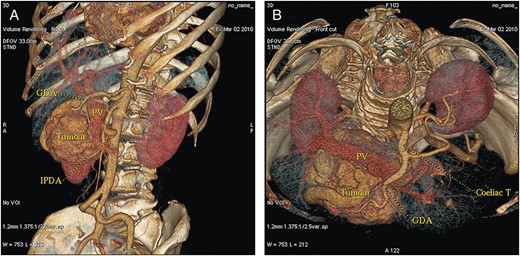

A 53-year-old, obese (body mass index 30.9 kg m−2), Caucasian woman was referred to our department with non-specific abdominal discomfort as the only presenting symptom. A large hypervascularized mass in the area of the pancreatic head was shown on abdominal ultrasonography and computed tomography (CT). There was neither lymphadenopathy nor distant spread found during pre-operative staging. Pre-operative imaging revealed an extremely hypervacularized tumour with abundant collateral vessels from the superior mesenteric artery (SMA), replaced right hepatic artery (HA), gastroduodenal artery (GDA) and right renal artery (RRA), with an early venous filling of the dilated superior mesenteric vein (SMV) and portal vein (PV) (Fig. 1A–C and Fig. 2A and B). The replaced right HA arising from SMA was crossing in between the dilated PV and overfilled tumour-draining veins (Fig. 1B). Abundant venous drainage was found. Extreme dilation of SMV and PV in both extra- and intra-hepatic course could be expected as numerous AV shunts within the tumour were present, but surprisingly, only a non-dilated, gracile splenic vein was found and no spleen enlargement was present (Fig. 1C). For better evaluation of vascular anatomy, selective digital substraction angiography (DSA) was performed. The upper portion of the tumour received main inflow via GDA and replaced right HA, the lower part via several branches of SMA (Fig. 3A and B). Capsular branch of RRA complemented tumour inflow (Fig. 3C).

(A and B) CT volume rendering images with dilated PV and an early contrast filling of dilated peritumoral veins.